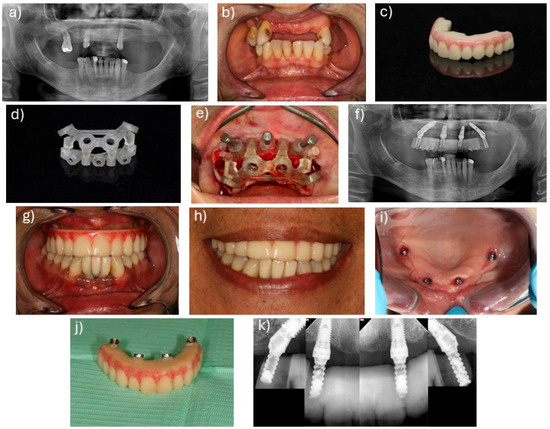

Digital Workflow for Interim Prosthetic Rehabilitation Through the All-on-4 Concept Using 3D Printing Additive Process

by Miguel de Araújo Nobre, Ricardo Almeida, Carlos Moura Guedes, Gonçalo Alvarez, Carolina Antunes, Ana Ferro, Mariana Nunes, Armando Lopes, João Rangel, João Pedro Martins, Diogo Santos and Miguel Gouveia

J. Clin. Med. 2025, 14(23), 8353; https://doi.org/10.3390/jcm14238353 - 24 Nov 2025

Background/Objectives: Fully digital workflows used in implant dentistry have been evolving to improve rehabilitation times and patient satisfaction. More studies are necessary for full scientific validation. The aim of this study was to evaluate the 6-month outcome of implant-supported fixed prostheses for [...] Read more.

Background/Objectives: Fully digital workflows used in implant dentistry have been evolving to improve rehabilitation times and patient satisfaction. More studies are necessary for full scientific validation. The aim of this study was to evaluate the 6-month outcome of implant-supported fixed prostheses for full edentulism rehabilitation using OnX Tough 2 resin (SprintRay) and the Pro 2 (SprintRay) 3D printer following the All-on-4 concept. Methods: This study included 16 patients (10 female, 6 male) with 20 implant-supported fixed full-arch prostheses following the All-on-4 concept (10 rehabilitations for each stackable guide and photogrammetry protocols). Primary The primary outcome measure was implant and prosthetic survival. The secondary outcome measures included manufacturing issues, prosthetic passive fit, marginal bone loss (MBL), mechanical and biological complications, modified plaque and bleeding indexes, pocket depths, patient subjective evaluation, and the Oral Health Impact Profile. Results: No patients were lost to follow-up. Two prostheses failed and 2 two implants were lost, resulting in a cumulative survival rate of 90% and 97.5% at 6 months for prostheses and implants, respectively. The mean MBL was 0.31 mm ± 0.52 mm at 4 months. The mechanical complications rate was 50% at patient level. One patient (6.3%) experienced one biological complication. The grades regarding “comfort of prostheses in the mouth” and “overall chewing feeling” were 9.35 ± 1.29 and 8.79 ± 1.67 out of 10, respectively. The mean total sum of the OHIP-14 was 1.61 out of 56. Conclusions: Implant-supported full-arch rehabilitations with fixed prostheses following the All-on-4 concept, through a fully digital workflow protocol, are a viable option in the short term. Full article